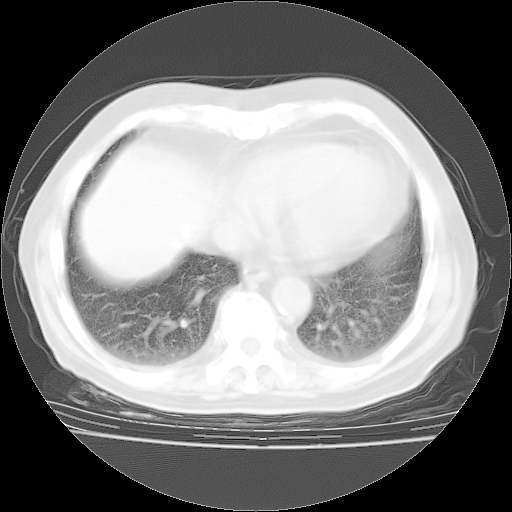

4月28日肺部CT——再次出现类似去年5月9日——透光度降低,“间质性”改变。

4月28日肺部CT——再次出现类似去年5月9日——磨玻璃样、间有“粟粒样”改变。

1、108#的是4月14日的胸部CT(发此贴时还没看着28日的CT)。14日的胸部CT其实已经出现改变(如108#所述),个人认为28日的胸部CT除纵膈窗疑似有双侧胸膜增厚或少量胸积液(可行胸部B超明确)外,与4月14日对照病变有所加重;2、已经给予“异烟肼、利福平、乙胺丁醇”抗痨治疗?如果是,甲强龙80mg可缓慢减量;如果环磷酰胺已停用,暂不使用;3、中性粒细胞92%,明显升高,目前体温情况?注意合并细菌感染可能,使用左氧氟沙星情况下,是否联用B-内酰胺类抗菌药物?另外是查免疫全套非风湿全套。

今请临免主任会诊后认为:4月14日胸部CT已有双下肺间质性改变。患者病情复发多系激素减量过快不正规所致。目前甲强龙80mg/日,一周后酌情开始减量,不易过快。环磷酰胺若已停用,暂不使用。他同意目前抗菌药物使用,但应考虑是否加用B-内酰胺类抗菌药物(中性细胞明显增高);2、结核复发目前依据不足;3、若免疫全套各项指标正常,考虑多系特发性肺间质炎可能大。4、加强支持,并注意保护胃黏膜。